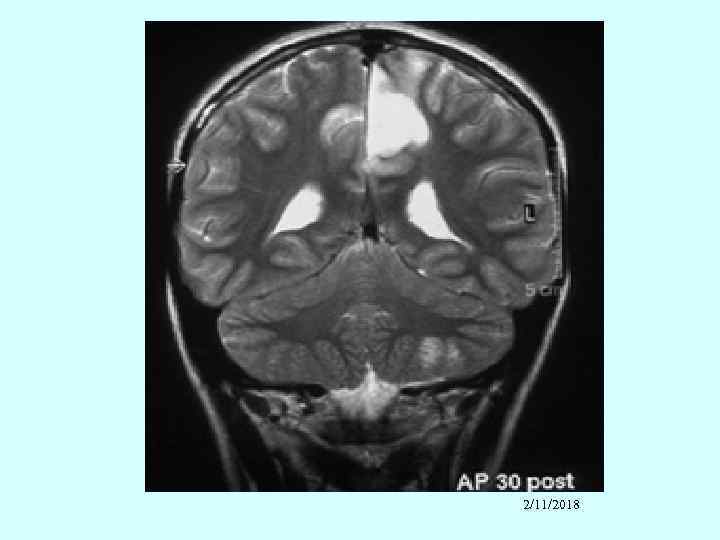

Neuropsychiatric • Diffuse CNS lupus • • • Cognitive dysfunction Headache Psychosis Seizures – can be any kind, usually grand mal Meningitis Focal cerebral dysfunction - Associated with antiphospholipid antibodies - Stroke (5%) 2/11/2018

Other neural system features • • • Peripheral neuropathy Cranial neuropathy – usually affects eyes Transverse myelitis Neuromyelitis optica Myelopathy Eye – cytoid bodies (vasculitis of retinal capillaries) _______________ Infection always must be excluded!!!!!! 2/11/2018

2/11/2018